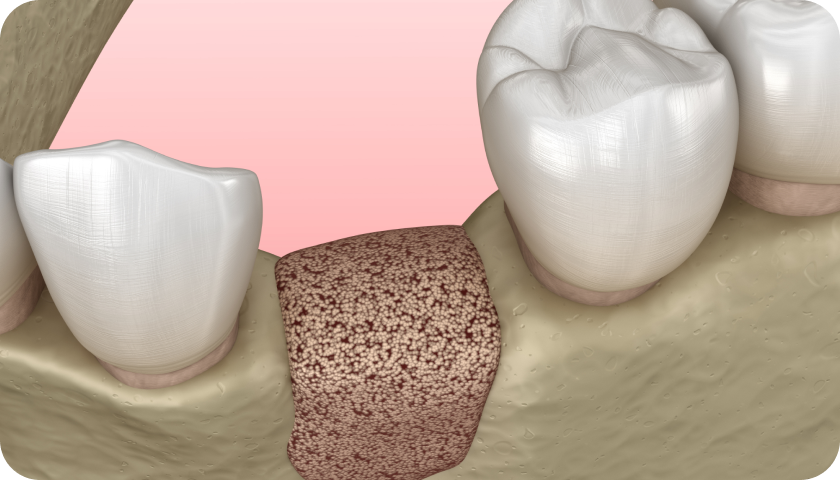

- Le prélèvement osseux : dans un second temps, le spécialiste va prélever le greffon osseux, le plus souvent au niveau de la mâchoire.

- La pose du greffon : après le prélèvement osseux, il sera temps de réaliser la greffe. Le Dr Bénichou réalisera alors une incision sur la zone à réparer, installera le greffon et apposera une membrane synthétique pour protéger la greffe de tout risque d’infection. Il ne lui restera alors qu’à suturer.

À l’issue de l’intervention de greffe osseuse dentaire à Toulouse, plusieurs rendez-vous pourront être fixés avec le dentiste, pour contrôler l’évolution de la cicatrisation. À terme, les sutures seront retirées. Une fois la zone totalement guérie, une opération d’implantologie dentaire pourra être programmée.